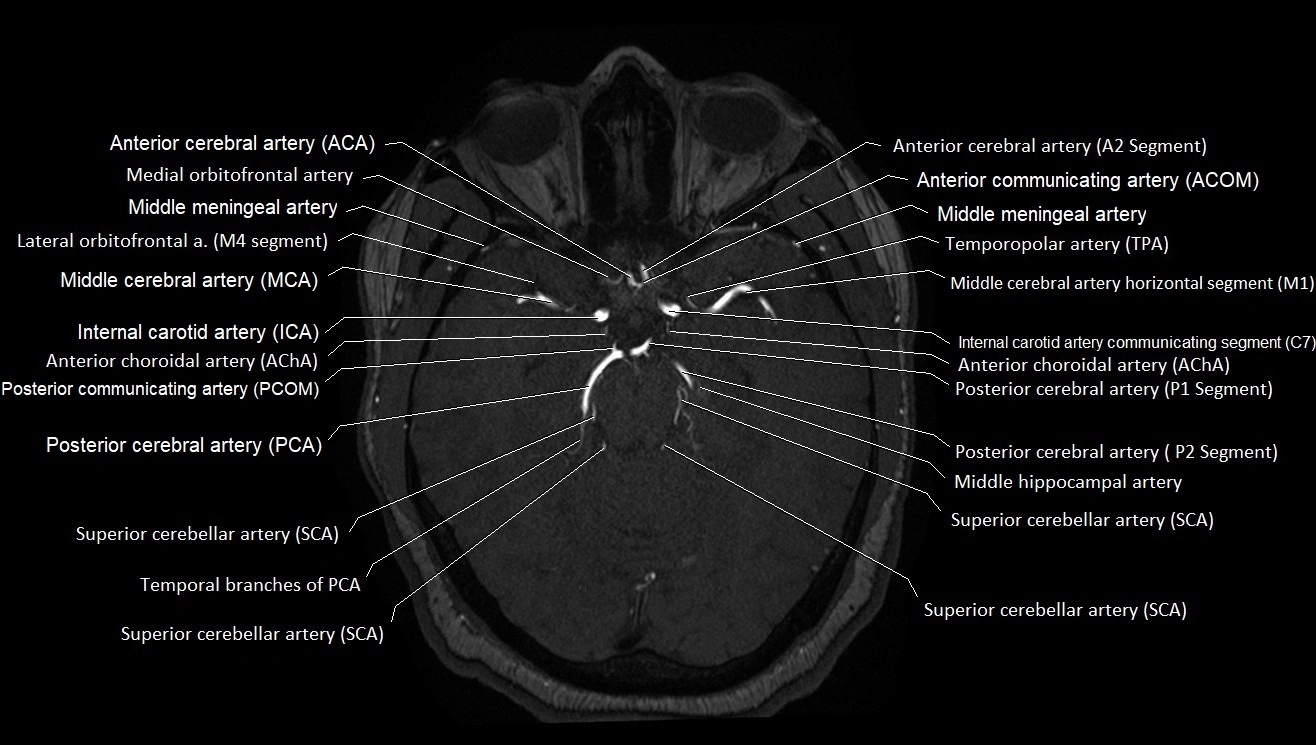

MRA (Magnetic Resonance Angiography):

• Flow-related enhancement makes the AChA appear as a bright, linear vascular signal against suppressed background

• High sensitivity for origin and proximal course; distal branches may be too small to resolve

• Detects stenosis, occlusion, aneurysm, AVM feeders